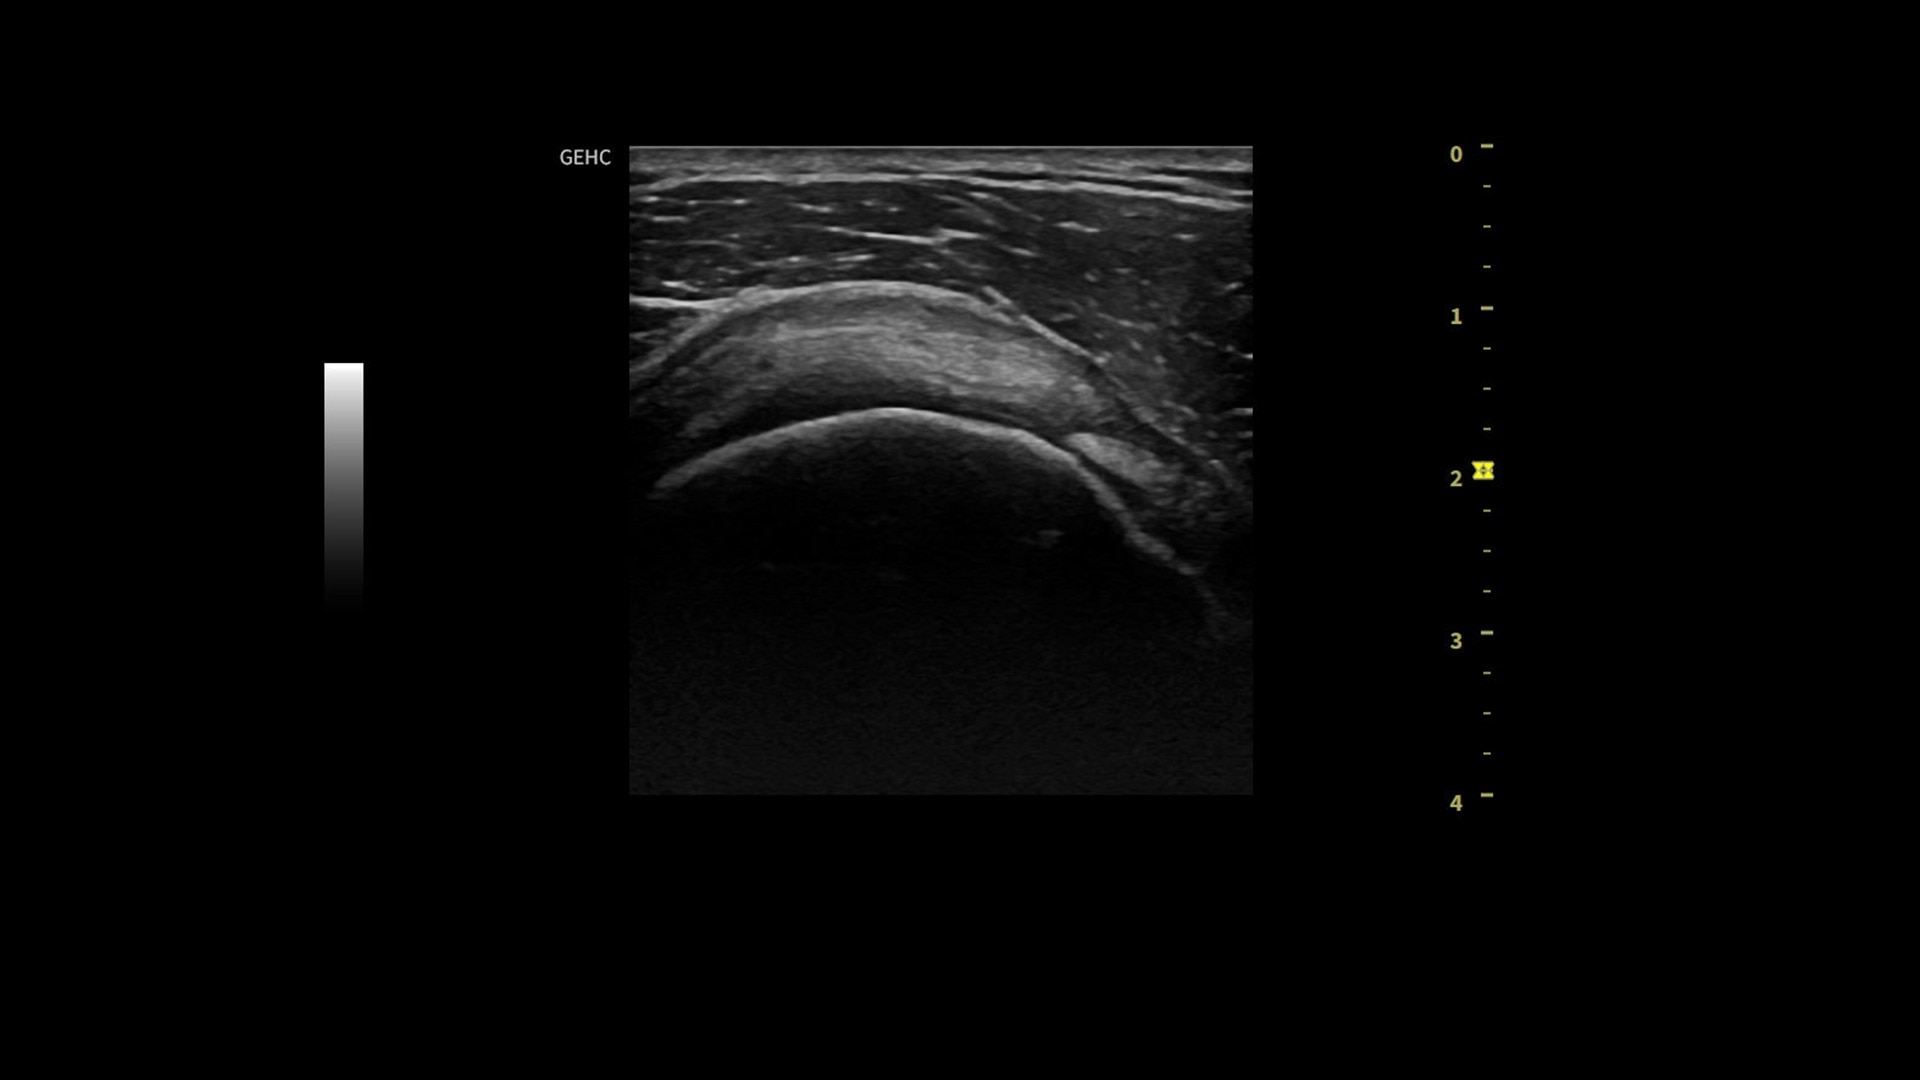

• Assess liver, thyroid and breast nodules with Productivity Packages leveraging LI-RADS,® TI-RADS® and BI-RADS® criteria*